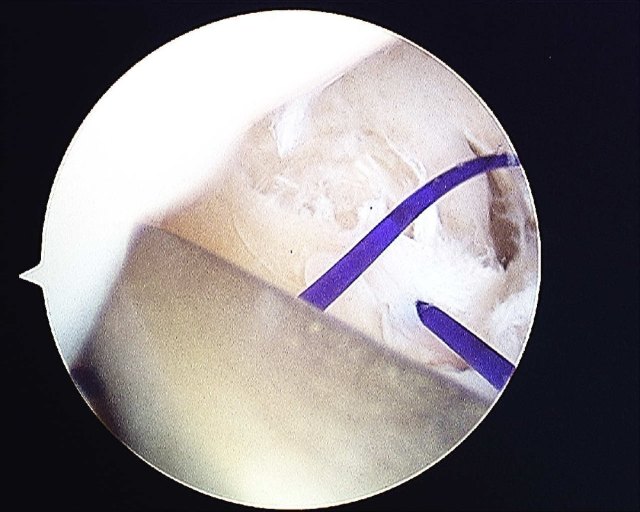

A PDS 3/0 suture is passed into the joint and retrieved through the 4/5 portal using a small arthroscopic grasper

The cannula is passed into the joint again to pass a suture shuttle. I use the PDS 3/0 as a suture shuttle.